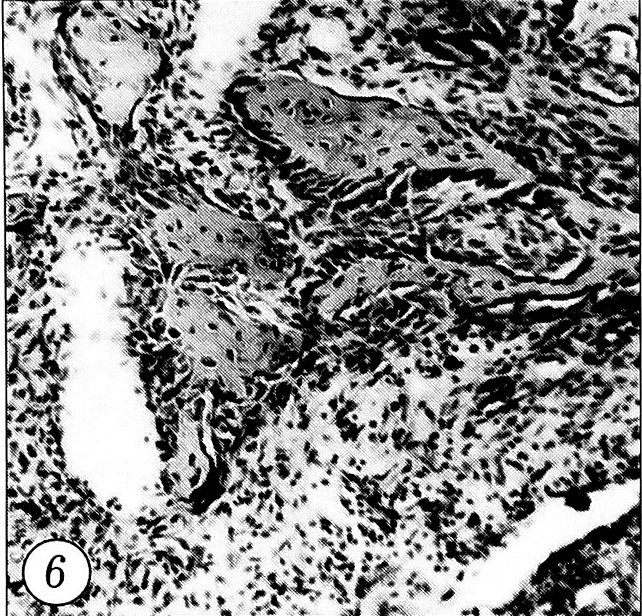

В 1-й (основной) группе воздействие на зону перелома НИЛИ приводило к существенному улучшению светооптической картины в области перелома уже на 3-и сутки. Плотность полиморфноклеточной инфильтрации была значительно меньше, чем в контроле. Увеличивалось число крупных остеобластов с гиперхромными ядрами и отмечалось образование новых костных трабекул (рис. 6), что свидетельствовало о стимуляции остеогенеза.

Рис. 6. Уменьшение полиморфно-клеточной инфильт-рации на поверхности кости, многочисленные остеобласты с гиперхромными ядрами вокруг новообразованных трабекул. 3-и сутки после перелома при лазеротерапии (окраска гематоксилином и эозином, об. 10, ок. 10).